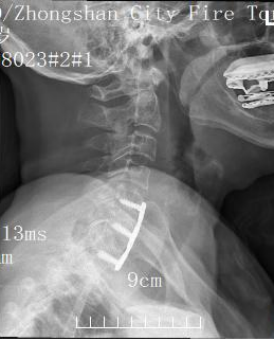

術(shù)中,團(tuán)隊通過頸部一個微小切口,精準(zhǔn)抵達(dá)頸7椎體骨折處,移除脊髓壓迫,徹底解除了對神經(jīng)的“枷鎖”,為神經(jīng)功能的恢復(fù)創(chuàng)造了空間。隨后,團(tuán)隊取患者自體髂骨進(jìn)行植骨,并植入一套精密的釘板系統(tǒng)進(jìn)行內(nèi)固定,成功重建了頸椎的穩(wěn)定性,猶如為受損的脊柱撐起了一座堅固的“內(nèi)部橋梁”。

術(shù)后X光片

整個手術(shù)過程順利,出血量少